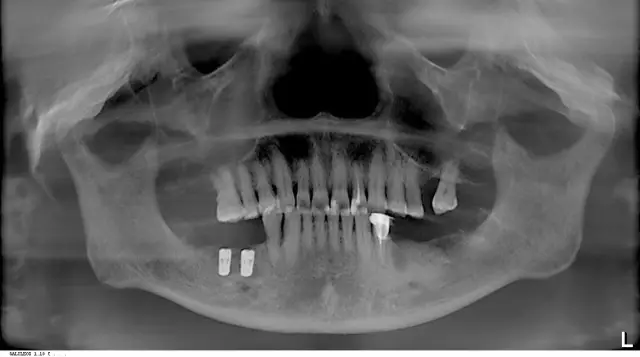

邹阿姨拔牙、种植后的牙片(先种一边,下次再种另一边)

在全面的口腔结构及骨质情况扫描后,王汉禹院长为饱受牙齿口腔困扰的叔叔阿姨们,就志愿者邹女士的牙片具体分析了其牙齿问题:因邹女士长期使用安装烤瓷牙的左侧吃饭咀嚼,时间一长牙根开始疼痛到不能忍受,来就诊一检查是牙根断裂了。他提醒老年人在进行口腔保健和治疗时不要图一时的方便便宜,要从长期治疗效果考虑。